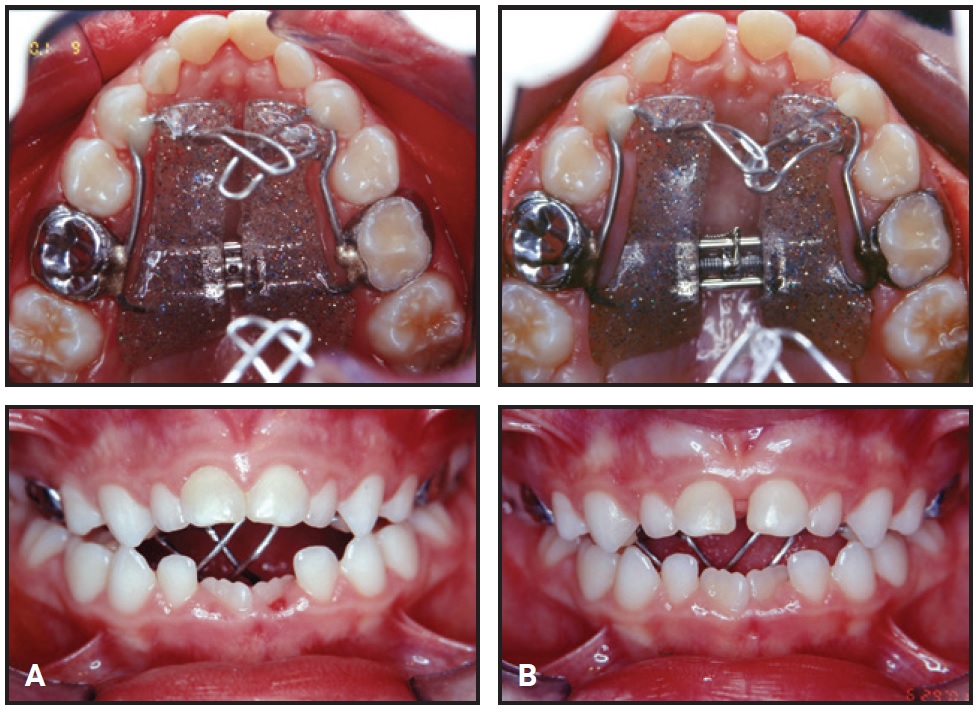

A modified Haas palatal expander with a palatal crib was installed to correct the posterior crossbite and anterior open bite (Fig. 2A). The screw was expanded with one-quarter turn daily for 28 days (Fig. 2B). Following a passive retention period and removal of the Haas expander, a fixed palatal crib was placed to prevent continued tongue thrusting and pacifier sucking. The interceptive phase lasted 20 months.

Fig. 2 Modified Haas palatal expander with palatal crib at time of insertion (A) and after 28 days of expansion (B).